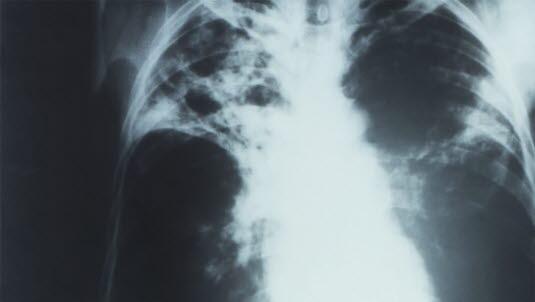

Foto: PHIL - CDC: Røntgenbilde (anterioposteriort) av en pasient med diagnosen avansert, aktiv, lungetuberkulose. Bildet viser bilateralt infiltrat og typisk tuberkulose-uthuling av høyre lungetopp.Foto: PHIL - CDC: Røntgenbilde (anterioposteriort) av en pasient med diagnosen avansert, aktiv, lungetuberkulose. Bildet viser bilateralt infiltrat og typisk tuberkulose-uthuling av høyre lungetopp.